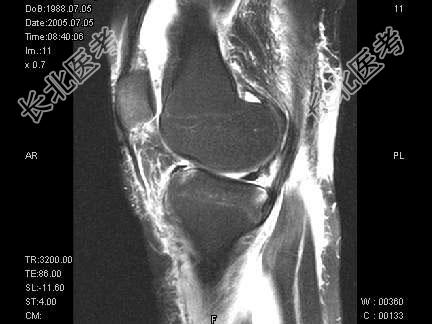

- 单项选择题女,17岁, 右膝关节有外伤史,现膝关节疼痛, 活动受限,结合图像, 最可能的诊断是 ( )

A、半月板撕裂

B、膝关节退变

C、未见异常

D、前交叉韧带断裂

E、后交叉韧带断裂